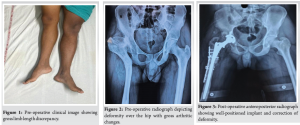

On examination, previous scar marks were visible over the hip and thigh, tenderness was present over the anterior joint line, and joint movements were restricted compared to the contralateral hip. Shortening of four cm was present over the right lower limb (Fig. 1). Radiograph of pelvis anteroposterior view revealed right dysplastic hip (Crowe’s type IV) with deformity over the shaft of the femur. Overriding of the greater trochanter and destruction of the femur head were noticed (Fig. 2). Further investigations were done, including computed tomography of the pelvis with bilateral hip and right femur for surgical planning. The patient was planned for subtrochanteric osteotomy plus THA.